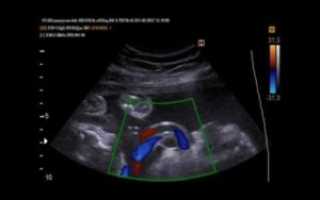

Киста пуповины у плода вызывает беспокойство у родителей и врачей, так как может указывать на осложнения в развитии ребенка. В статье рассмотрим причины возникновения кисты, ее риски и последствия для здоровья плода. Понимание этой темы поможет родителям и медицинским специалистам принимать обоснованные решения и своевременно реагировать на проблемы, что повлияет на здоровье новорожденного.

Не игнорируйте ультразвуковые исследования. Они помогают выявить кисты и другие аномалии на ранних стадиях, что позволяет своевременно принять меры и снизить риски для здоровья ребенка.